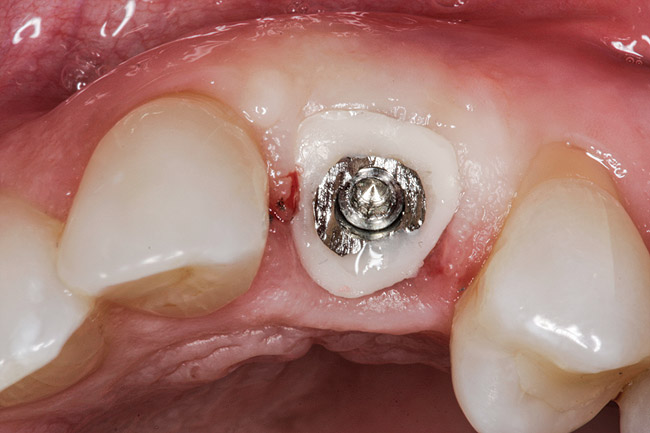

Blanching of the soft tissue.

Figure 7

The provisional is then trimmed of flash and polished, placed into the mouth, and hand tightened. Blanching of the soft tissue is seen as the result of the tissue slumping without the support of the tooth (Figure 7). The provisional is evaluated for proper free gingival margin positioning. The interdental papilla are assessed for volume and height, and the occlusion is checked. If there are any shortcomings, the provisional contours are adjusted. If the gingival margins are more apical than ideal, the cervical area of the provisional is relieved. If the free gingival margin is more coronal than the ideal position, the cervical area of the provisional is bulked out to move the soft tissue apically. Interdental papilla are altered by changing the contact point position, volume, and convexity of the proximal surfaces.10,11 Once the esthetic contours have been developed, a cotton pellet is placed over the screw head, the access hole is filled in with the material of choice, and the occlusion is checked. The goal is to achieve minimal centric contact with no contact in lateral excursions.